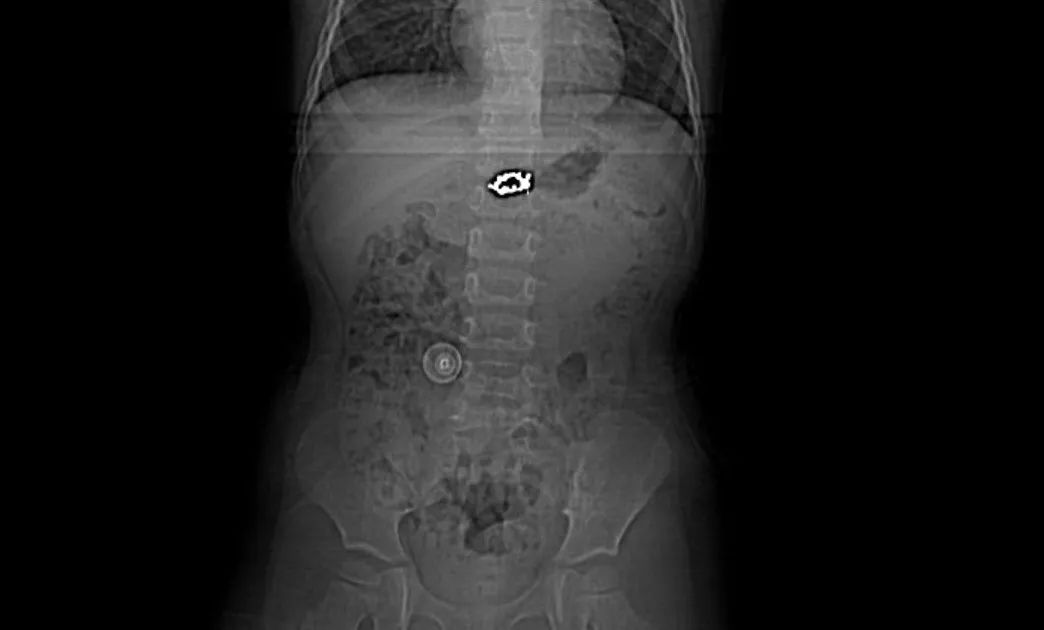

据了解,7月4日,一名年仅3岁的女童在玩耍时,不慎将母亲的一枚金属耳环吞入腹中。家长发现后,立即将孩子送至云县人民医院就诊。经儿科医生接诊后,转诊消化内科,经检查,确认这枚直径约2厘米的金属耳环滞留在女童胃内,存在划伤消化道甚至引发梗阻、穿孔等严重风险。

考虑到异物较大且材质坚硬,消化内科团队迅速决定采用无痛胃镜技术进行紧急取出。在麻醉科配合下,手术顺利进行。医生通过胃镜精准定位异物,并使用专用器械,小心地将耳环从女童胃内完整取出。术后,女童恢复良好,未造成消化道损伤。